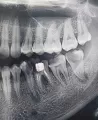

Также на 6 внизу на снимке показано, что есть воспаление (10 лет назад нервы удалены, каналы запломбированы), побаливает при жевании твердой пищи и ноет периодически. Также на некоторых других зубах есть кариес.

Восьмые зубы необходимо удалить все, можно оставить только 48, он стоит в зубном ряду и не создаёт скученность, и не страдает соседняя семерка. Во всех трёх остальных случаях Ваши зубы мудрости необходимо удалить как можно раньше.

На обеих нижних шестёрках имеется хронический воспалительный процесс обширных размеров, и если Вы незамедлительно не займётесь лечением, то вскоре мы получим капсулированную кисту, и как следствие, удаление.